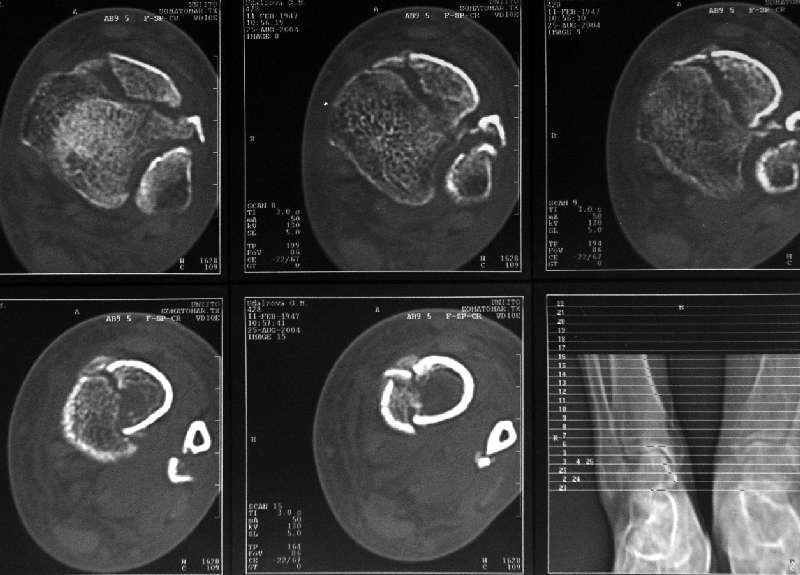

Дама 56 лет 6 недель назад получила спиральные переломы дистальных отделов костей голени. По месту жительства наложили гипс.

Сейчас вот, получается, спохватились. Снимки и КТ в приложении. Какой вариант тут предпочтительнее - открытая мобилизация, репозиция и внутренняя или наружная фиксация? Или ограничиться только резекцией костного шипа над шейкой тарана?Заранее спасибо.A female 56 y.o. 6 weeks ago sustained a fracture of the distal tibia/fibula. At the initial hospital a plaster cast was applied. Now she was referred to our unit. At the moment there is no pain, no obvious mobility. Images and CT attached.What is the best option here? Mobilize the fracture, perform open reduction and internal or external fixation? Or just to cut the anterior spike over the talar neck? THX in advance.

The anterior spike seems to be more antero-lateral, rather than anterior, in such a position that it may not hamper dorsiflexion.

The ankle mortise as a unit is intact.

I would therefore only remove the anterior spike, if it impedes dorsiflexion.